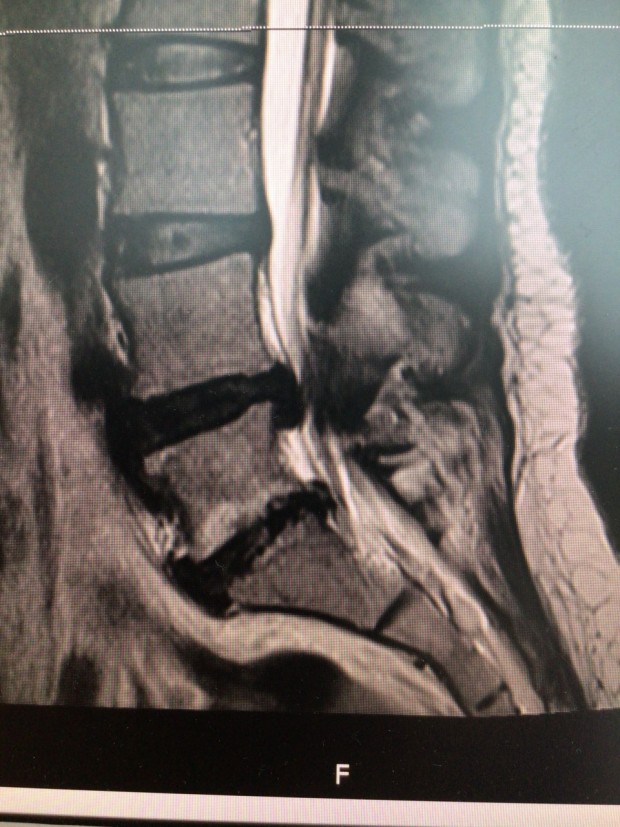

척추수술이야 특별한 것이 있겠냐 마는

디스크 돌출부분을 자르고 눌린 부분을 풀어주고,

디스크가 다시 나오거나 움직이지 않게 그 인접뼈들을 고정하는게 기본적인 척추 수술의 원리입니다.

이 처럼 수요가 많지 않다 수요가 폭발한 것 처럼, 척추수술도 생각보다 수술이 간편하고 회복이 빨라지면서 관절경 수술수가 늘어나고 있습니다. 척추도 병변이 미세하게 작은 부분이라면 작은 절개창으로 그 부분만 수술 하므로써 증상 호전이 쉽게 가능하게 된다는 개념입니다.